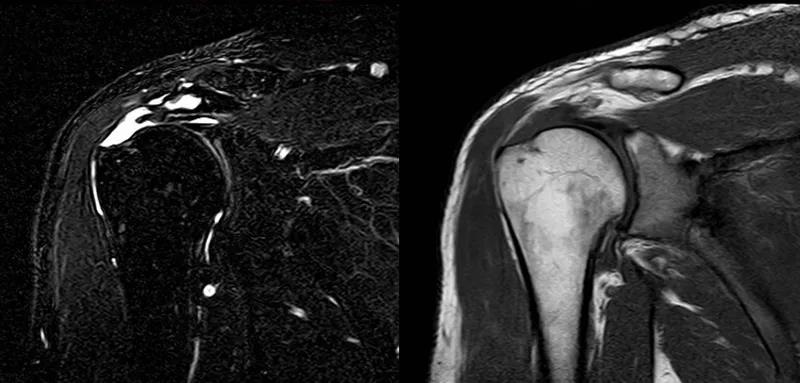

图24 a.肩袖全层撕裂;b.正常MRI